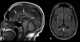

Marchiafava–Bignami disease is a progressive neurological disease of alcoholism, characterized by corpus callosum demyelination and necrosis and subsequent atrophy. The disease was first described in 1903 by the Italian pathologists Amico Bignami and Ettore Marchiafava in an Italian Chianti drinker. [Source: Wikipedia ]